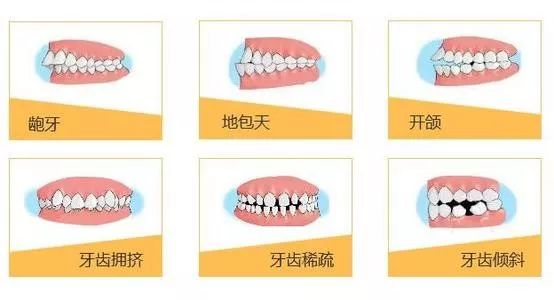

小儿牙齿畸形

小儿牙齿畸形